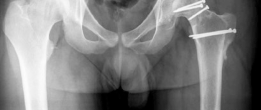

Following the resection of the wedge, the remaining viable segments of the femoral head are approximated. The reduction must restore a spherical contour that matches the native acetabular radius of curvature.

Fixation is achieved using multiple countersunk headless compression screws or bioabsorbable pins. The trajectory of the screws must be meticulously planned to cross the osteotomy site perpendicularly, maximizing interfragmentary compression while avoiding penetration into the articular surface or the vital posterior retinacular vessels. Fluoroscopy is utilized to confirm anatomic reduction, appropriate screw length, and the absence of intra-articular hardware.

The hip is then reduced back into the acetabulum. The joint is taken through a full range of motion to confirm the resolution of hinge abduction and the restoration of impingement-free kinematics. The capsule is closed loosely to prevent postoperative intra-articular hypertension. The trochanteric flip osteotomy is reduced and fixed using two or three 4.5 millimeter cortical screws.